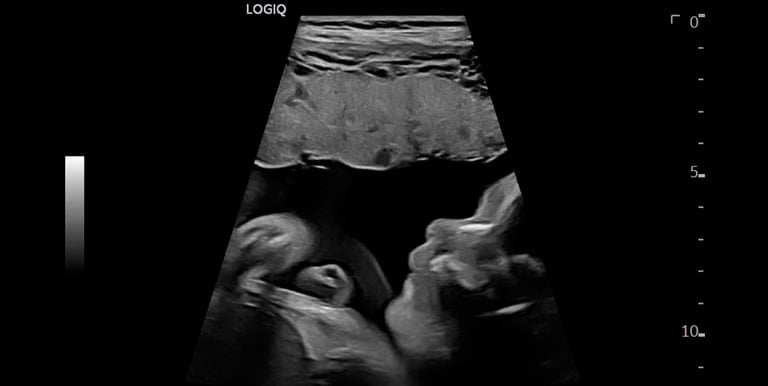

Obstetric Care

Caring ultrasound services supporting you through every pregnancy stage.